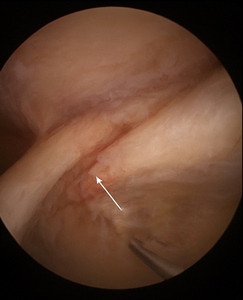

Diagnostic arthroscopy confirmed a well-defined intrasubstance split in the upper subscapularis fibers with fraying but preserved lateral insertion (Figure 2). The lesion was repaired transtendinously using a knotless all-suture anchor system, allowing preservation of intact lateral fibers. Stability was restored following fixation, with no iatrogenic injury to adjacent structures.